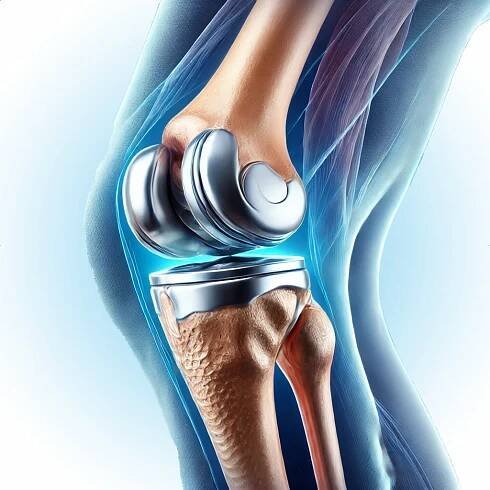

Totální endoprotéza kolenního kloubu je chirurgický zákrok, který se provádí při pokročilém poškození kolenního kloubu. Jedná se o nahrazení poškozených částí kloubu umělými implantáty, které obnovují pohyb a funkci kloubu.

Kolenní kloub je nejsložitější a největší nosný kloub v lidském těle. Je klíčový pro náš pohyb, ale jeho nadměrné opotřebení způsobovje často bolest, omezení pohyblivosti a v některých případech i vznik osové deformity.

Totální náhradu kolenního kloubu indikujeme pro pokročilé degenerativní, poúrazové, metabolické či zánětlivé postižení kolene, způsobující pacientům velké bolesti a funkční omezení, která již nereagují na konzervativní terapii.